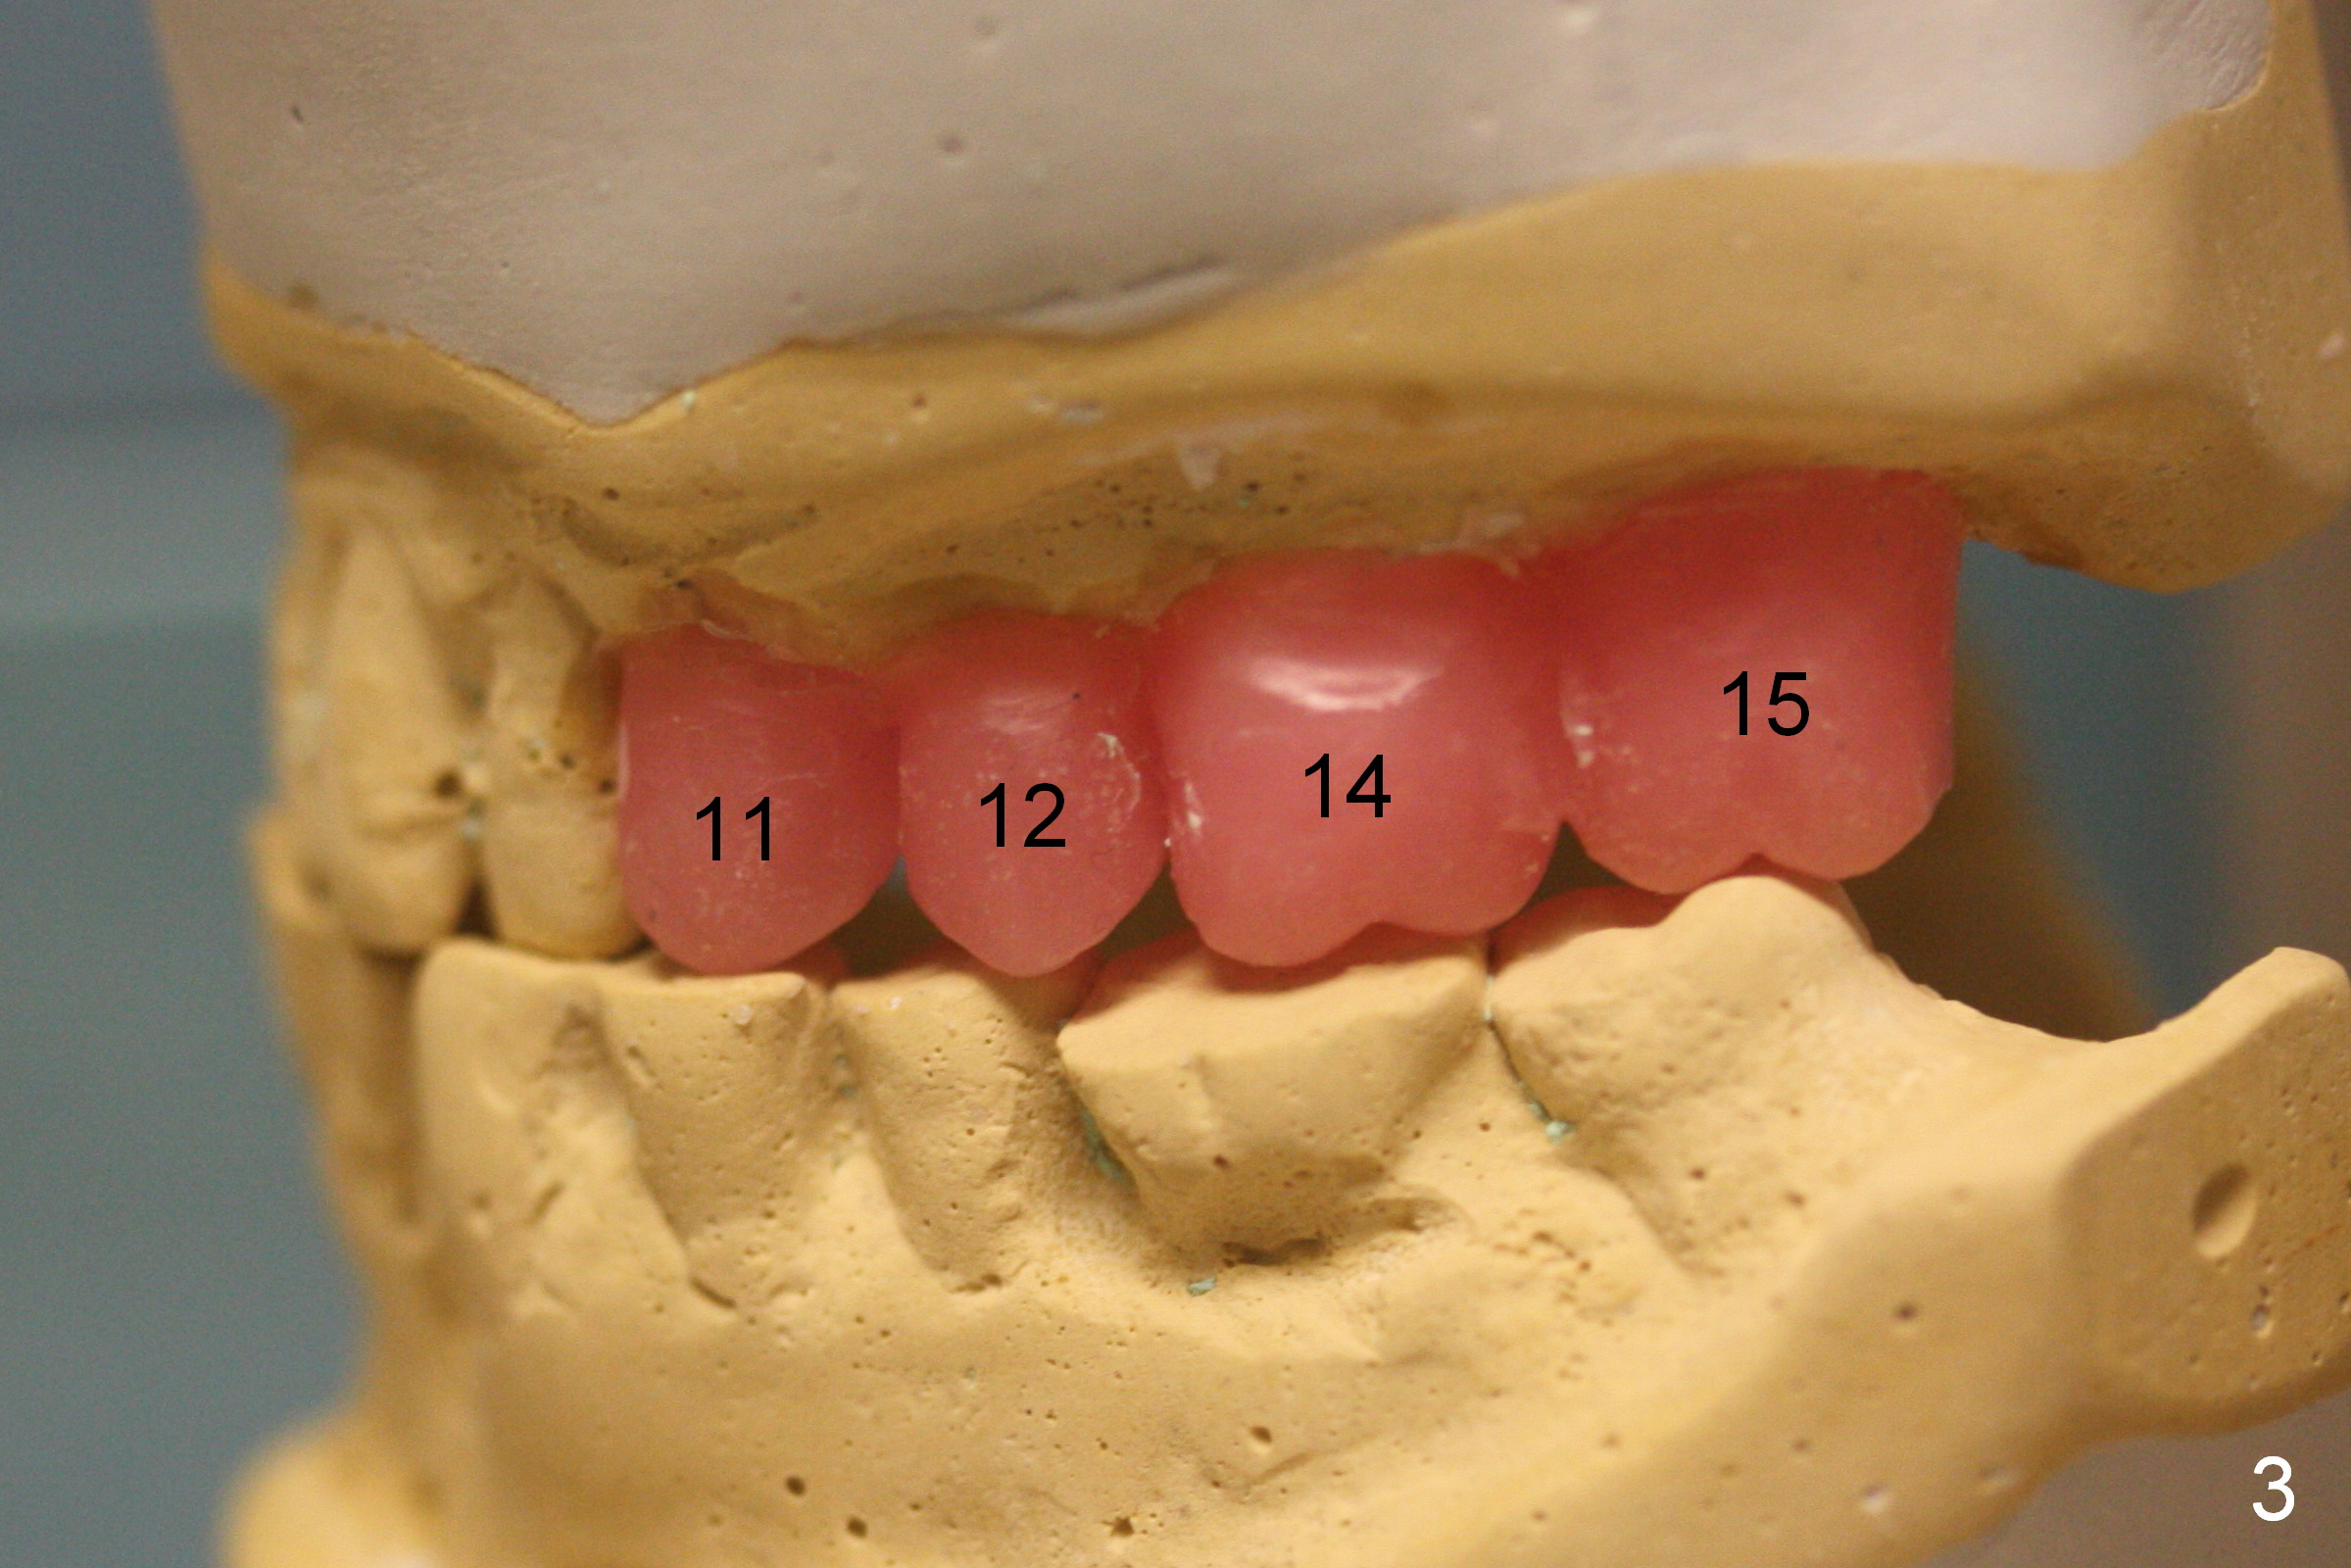

A 70-year-old man (CK) requests restoration of the upper arch with implants, because he is not used to a partial denture. Due to cross bite (Fig.1-3), one less implant can be placed in each of the posterior region (Fig.1, 3).

To avoid or reduce the chance of using an angled abutment at #6, the apical end of the implant should be placed as close to the buccal plate as possible (Fig.8 red arrow). Compare the angles at the implant crown (Fig.7,8). Initial osteotomy depth is 17 mm; insert parallel pins and take PA for checking trajectory (Fig.4). When fabricating provisional crowns, make sure that they are palatal to the lower counterparts (cross bite), both right and left.